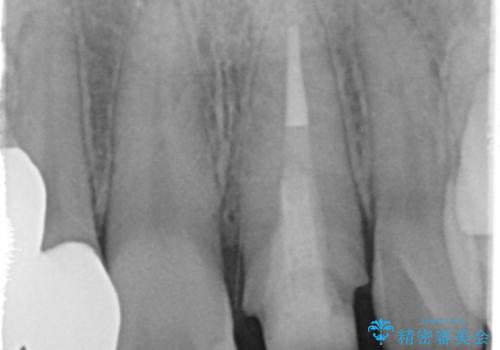

歯ぐきの状態も良く、適合の良い被せ物を入れることができました。

審美性もかなり改善され、大変喜んでいただけました。